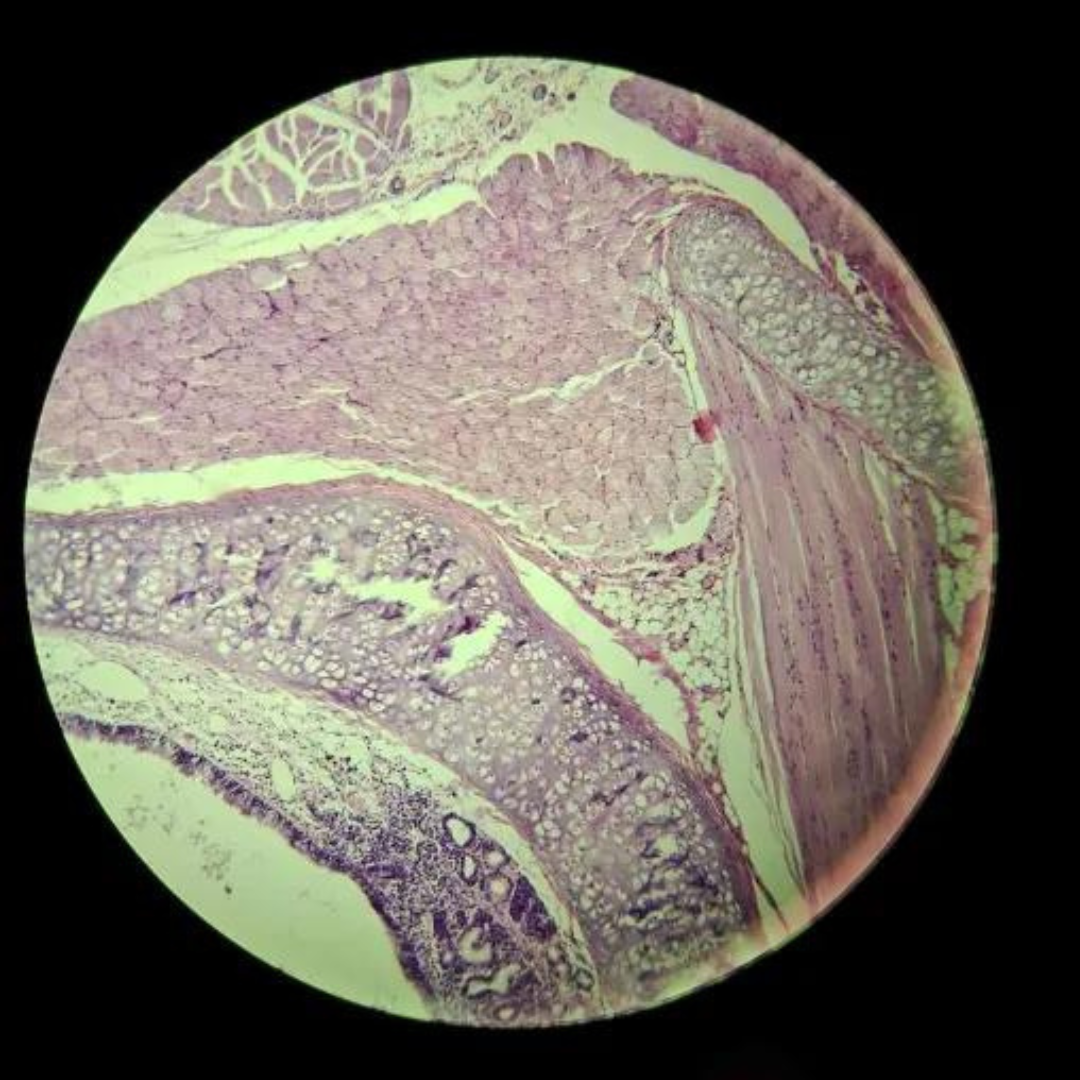

Jejunum

Duodenum

Jejunum

Jejunum

Jejunum

Jejunum

Jejunum

Jejunum